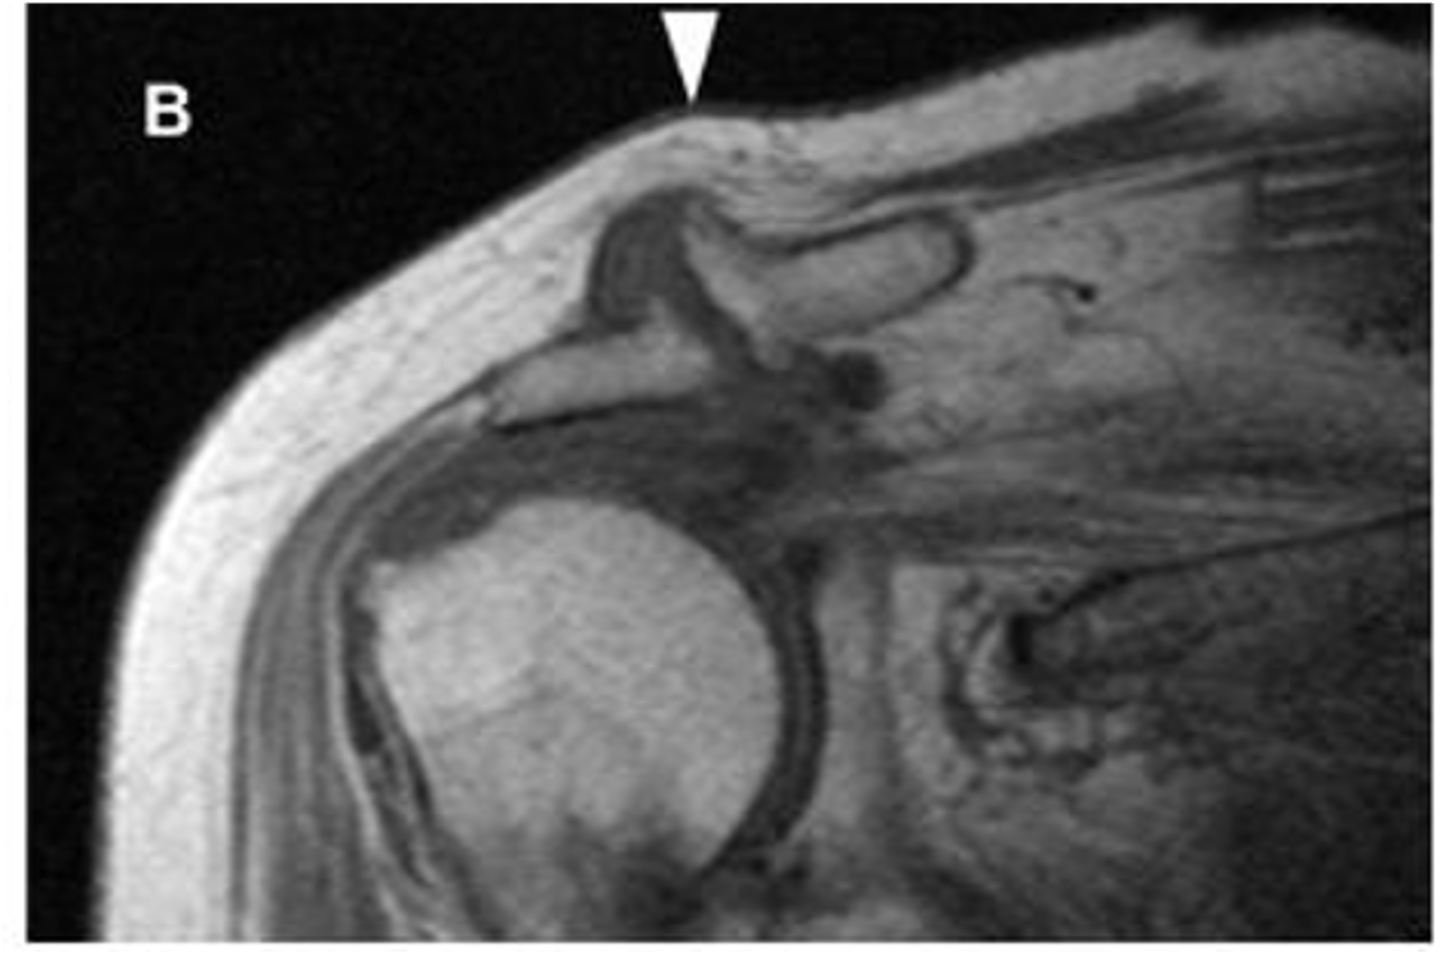

Adhesive capsulitis (frozen shoulder) -- axillary recess can get fibrose, thick, and larger than normal

Note: typically, MRIs should NOT be ordered for adhesive capsulitis because they're not necessary

What is this image depicting? How do you know?

**ALTHOUGH THIS IS IN THE ADHESIVE CAPSULITIS SECTION, DR. C SAID THAT THIS IS A CRAPPY EXAMPLE AND IS ACTUALLY A NORMAL AXILLARY RECESS THAT IS BEING HIGHLIGHTED BY THE DYE IN THE MRI ARTHROGRAM**

Note: normally, you DON'T see the axillary recess very easily, but in this image, the dye makes it clear as day

What is this image depicting?

1. When there is a labral tear, the dye will make its way into that region, as depicted in this image

2. ADHESIVE CAPSULITIS IS NOT PRESENT -- THIS IS A NORMAL PRESENTATION DUE TO THE DYE IN THE RECESS

Two questions for you on this one: why do we know there a labral pathology present? (1) and why is this NOT adhesive capsulitis? (2)

THEN, that would be considered full-blown adhesive capsulitis

Essentially, if there IS dye, it's always going to look like there's something going on with the axillary recessive. What about if there was NO dye?